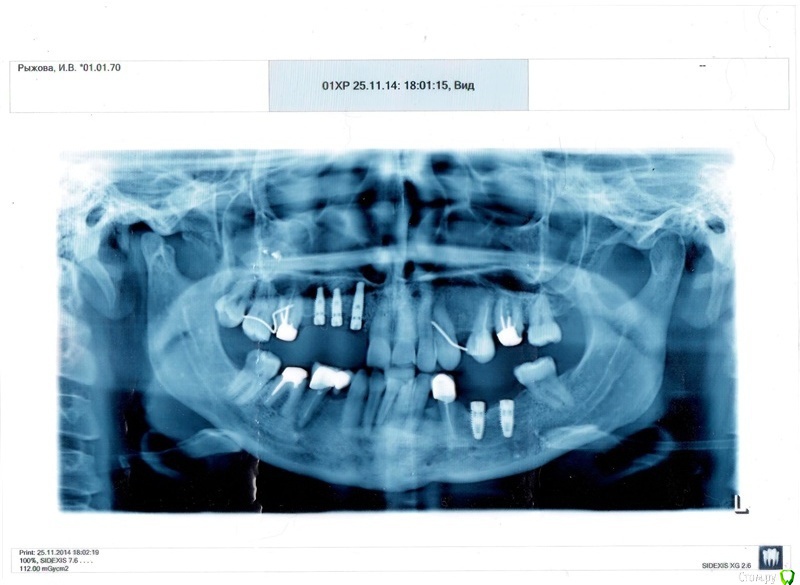

Andrej Опубликовано 2 июля, 2015 Поделиться Опубликовано 2 июля, 2015 Уважаемые специалисты,что скажете по поводу необходимости установки подковы на ВЧ? На фото моя жена Снимок немного устарел, на данный момент уже удалён средний имплант на ВЧ, зубы 18, 16.Средний имплант был с внешней стороны обнажён (виднелась резьба), т.к. рассосалась кость, и его безжалостно удалили,пояснив что достаточно и двух имплантов. Удалился он одним движением, сам видел. В отверстие от удалённого импланта и 16 зуба поставили кость, всё прижилось, всё нормально.Также удалены нижние 45, 46, вместо них установлены 2 импланта. На нижнюю челюсть ставим по мосту на имплантах с каждой стороны, т.е. по 3 МК коронки на 2 импланта. И то, врачи хотят захватить этими мостами по одному соседнему зубу, вроде как для снижения нагрузки на импланты, ибо это область жевания. Но вроде, импланты и зубы лучше под одним мостом не объединять, поэтому бодаемся с ними и по этому вопросу.Но главный вопрос всё-таки по ВЧ. Мы бы хотели МК мостик на имеющиеся импланты на ВЧ, да подправить коронку на 26, и достаточно. Нам же предлагают либо подкову, либо идти в другую клинику... Мотивируют тем, что остальные зубы на ВЧ плохие, слабые, а подкова придаст им жёсткости. А наш вариант для них не вариант, потому что у них репутация. Хвалятся, что протезист у них супер-пупер, профессор и все дела. Лечимся в Белграде, Сербия.Как считаете, стоит ли связываться с подковой? Ссылка на комментарий